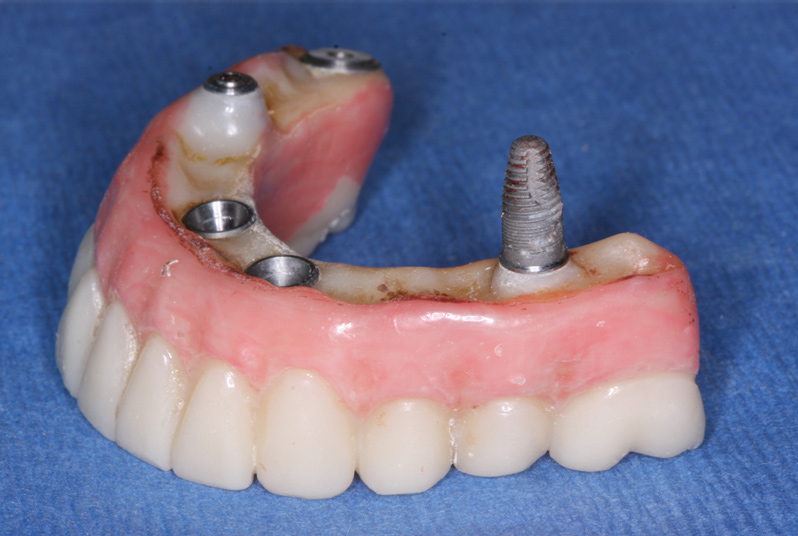

Anesthesia was administered, after which the retaining screws were removed from the PMMA interim screw-retained prosthesis beginning at the distal left. However, the distal right screw could not be removed; the prosthesis and implant came out as one unit after pulling (Figure 13). Based on the distance between where the implant had been and where the next implant was in the front (ie, one of the newly placed implants), engagement of the interim screw-retained prosthesis would now have to occur at the previously placed implant site. However, because the laboratory advised that the implant at that site should be buried, resulting in a potentially large cantilever on the posterior right side, three options were considered:

Fig 13. The posterior right screw retaining the PMMA prosthesis the patient wore for 2 months did not come out until the prosthesis was pulled, at which time the entire implant came out.

Figure 13